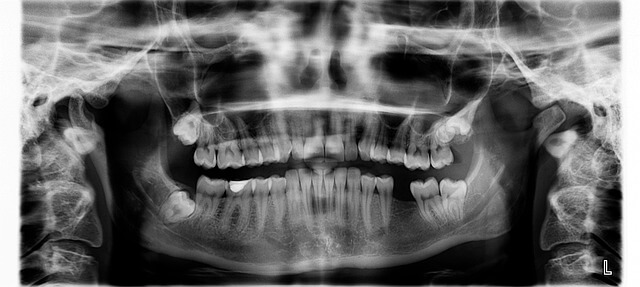

또한, 노화에 따른 침샘 기능 저하도 구강건조증 원인으로 매우 흔합니다. 60세 이상 고령자는 자연스럽게 침 분비가 줄면서 입술이 갈라지고, 미각 감소와 충치 위험 증가가 나타나죠. 평소 1분당 0.1ml 이하의 침 분비는 구강건조증 원인에서 침샘 기능 저하를 의미하며, 꾸준한 수분 섭취와 구강 보습이 필요합니다.